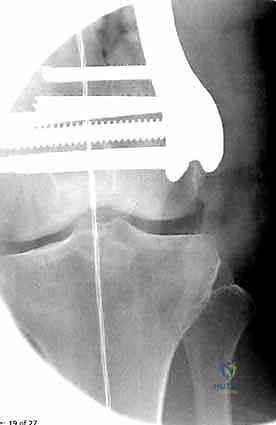

- الأشعة السينية (X-Rays): أخذ صور من زوايا متعددة (أمامي خلفي، وجانبي) لتحديد موقع الكسر ونوعه.

- الأشعة المقطعية (CT Scan): وهي ضرورية جداً في كسور عظم الفخذ البعيدة، خاصة إذا كان الكسر يمتد إلى داخل مفصل الركبة (Intra-articular fractures). تساعد الأشعة المقطعية الدكتور هطيف على بناء نموذج ثلاثي الأبعاد للكسر، مما يسهل التخطيط الجراحي وتحديد أماكن وضع المسامير بدقة.

المرحلة الرابعة: التثبيت النهائي بالشرائح والمسامير (Fixation)

يتم استخدام "شرائح الإغلاق التشريحية" (Anatomical Locking Plates) المصنوعة من التيتانيوم عالي الجودة. هذه الشرائح مصممة خصيصاً لتأخذ شكل الجزء السفلي من عظم الفخذ. يتم تمرير الشريحة أسفل العضلات وتثبيتها بمسامير تغلق داخل الشريحة نفسها (Locking Screws)، مما يوفر ثباتاً ميكانيكياً هائلاً، حتى في حالات العظام الهشة.

في بعض الحالات المعقدة جداً، قد يتطلب الأمر استخدام شريحتين (Dual Plating) لضمان عدم تحرك الكسر أثناء فترة التعافي.